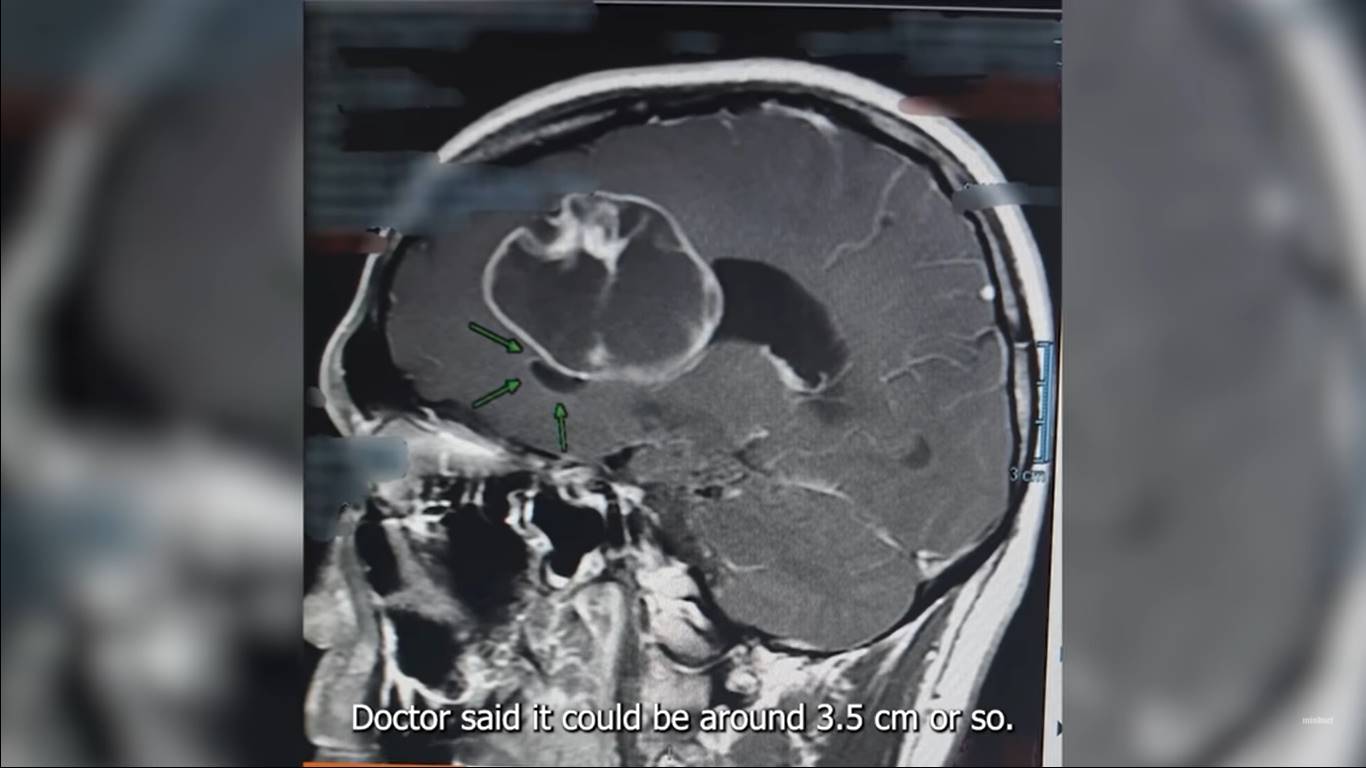

อาการเริ่มต้นเกิดจากอาหารหูอื้อ ตอนแรกไปหาหมอหู ตา จมูก ก็ไม่พบความผิดปกติ แต่อาการก็เริ่มหนักขึ้น เริ่มปวดท้ายทอย ปวดขมับ ปวดทุกอย่างพร้อมกันหมด ปวดจนถึงขนาดรู้สึกว่าจะล้ม ต้องหาอะไรมาจับตลอดเวลา เรียกว่าวิกฤตเลยทีเดียว จึงตัดสินใจไปหาหมอทางด้านสมอง และได้ทำ MRI กระทั่งได้เจอกับสิ่งที่ไม่คาดคิดว่าะจะเกิดขึ้นในชีวิตก็คือ "ก้อนเนื้องอกในสมอง"

หลังจากเจอเนื้องอกแล้ว หมอก็แนะนำว่าให้ผ่าออกโดยเร็วที่สุด ผ่าโดยการเปิดกะโหลก ไม่ใช่แค่ส่องกล้องผ่า เบื้องต้นคาดว่าขนาดประมาณลูกปิงปอง 3.5 เซนติเมตร